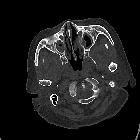

CT

- non-contrast CT

- sinonasal mucosal thickening +/- air-fluid levels +/- soft tissue nodules

- bony/cartilaginous erosions, in particular, affecting lamina papyracea, nasal septum, and lateral nasal cavity wall +/- perforation

- post-contrast CT

- enhancing soft tissue nodules